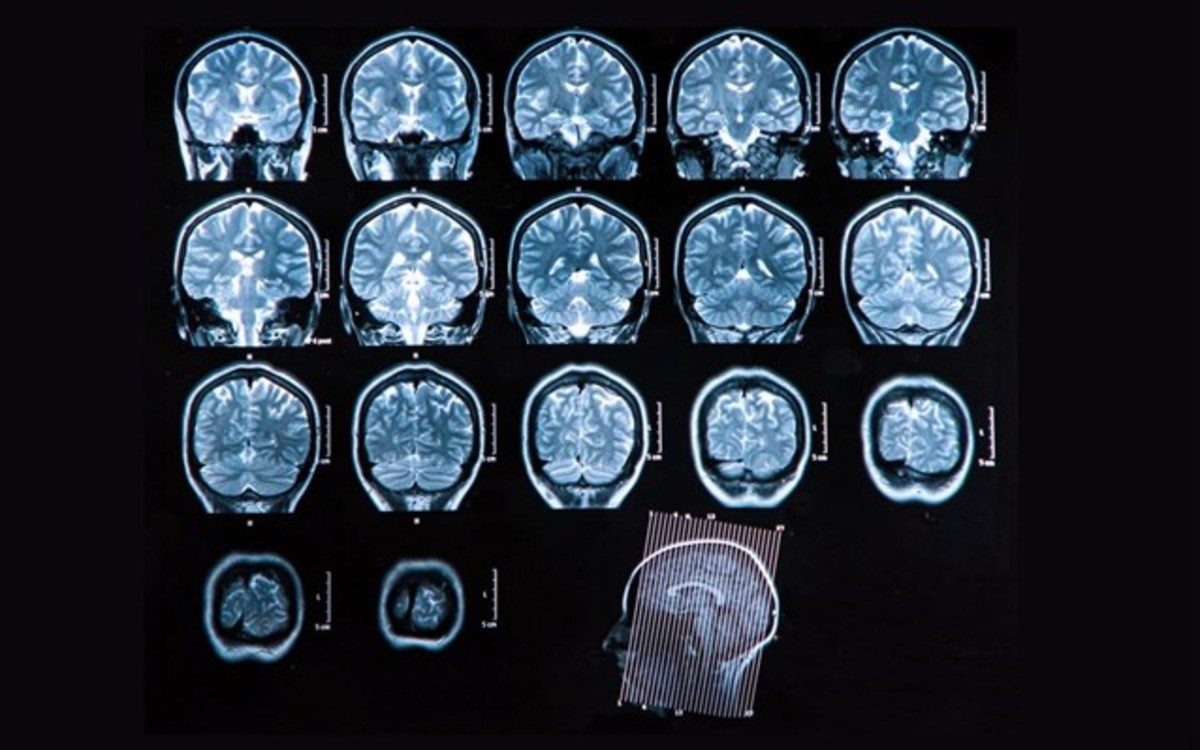

Νέα θεραπεία για την αναχαίτιση της σκλήρυνσης κατά πλάκας

Επιστήμονες ανακάλυψαν ότι μπλοκάροντας ένα συγκεκριμένο μόριο που διαταράσσει το ανοσοποιητικό σύστημα είχε ως αποτέλεσμα την μείωση έως και κατά 50% της σκλήρυνσης κατά πλάκας σε ποντίκια με τα συμπτώματα της νόσου.

Το μόριο κυτταρικής προσκόλλησης MCAM (Melanoma Cell Adhesion Molecule) είναι το «διαβατήριο» για δύο τύπους λευκών αιμοσφαιρίων, τα CD4 και CD8, τα οποία διαπερνούν τον αιματοεγκεφαλικό φραγμό του εγκεφάλου και εισβάλλουν στο κεντρικό νευρικό σύστημα προκαλώντας τις βλάβες που συνδέονται με την σκλήρυνση κατά πλάκας. Ερευνητές από το Πανεπιστήμιο του Μόντρεαλ στον Καναδά λένε ότι ένα φάρμακο που θα μπλοκάρει το συγκεκριμένο μόριο σε ανθρώπους θα μπορούσε να καθυστερήσει την εκδήλωση των συμπτωμάτων της νόσου και να αναχαιτίσει την εξέλιξή της.

Σύμφωνα με τα πολλά υποσχόμενα αποτελέσματα δοκιμών σε ποντίκια, οι επιστήμονες διεπίστωσαν υποχώρηση της νόσου σχεδόν κατά το ήμισυ και όπως τονίζουν στην επιθεώρηση Annals of Neurology, για πρώτη φορά κατάφεραν να σταματήσουν την ασθένεια από τα πρώτα κιόλας συμπτώματα, πέραν του αντίκτυπου που είχε το μπλοκάρισμα του MCAM στην πρόοδο της. «Πιστεύουμε ότι προσδιορίσαμε την πρώτη θεραπεία που θα επηρεάσει την ποιότητα ζωής πασχόντων από σκλήρυνση κατά πλάκας μειώνοντας σημαντικά την αναπηρία και την πρόοδο της νόσου» λέει ο καθηγητής Νευροεπιστημών και επικεφαλής της σχετικής μελέτης Alexandre Prat.

Γι’ αυτήν την μελέτη, η ερευνητική του ομάδα συνεργάσθηκε με την Prothena Biosciences, μια ιδιωτική εταιρία με έδρα το Σαν Φρανσίσκο στην Καλιφόρνια. Το πειραματικό φάρμακο PRX003 που έχει αναπτύξει η εταιρία για να μπλοκάρει το MCAM φράζοντας τον δρόμο στα λευκά αιμοσφαίρια πριν περάσουν στο κεντρικό νευρικό σύστημα, πρόκειται να δοκιμαστεί κλινικώς σε υγιείς εθελοντές στα τέλη του προσεχούς Ιουνίου.